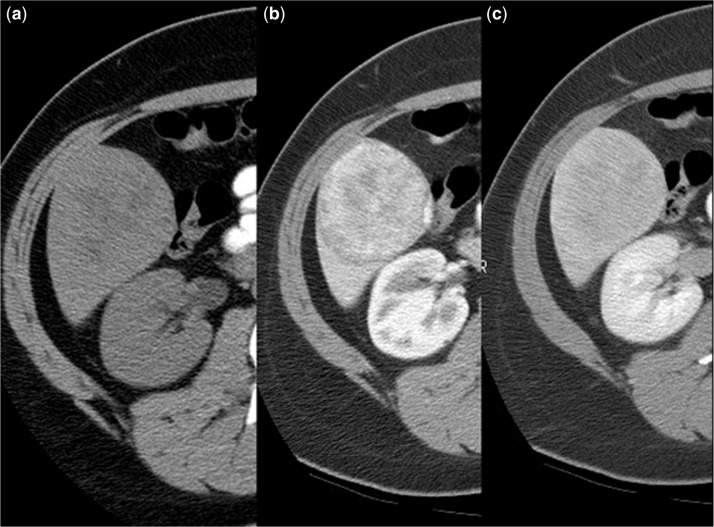

On unenhanced CT (Fig. 6a), uncomplicated HAs are isodense or hypodense to the surrounding liver. Hyperdense areas corresponding to hemorrhage can be noted as well. Low-density regions may correspond to regions of intratumoral fat. Following contrast administration, CT (Fig. 6b,c) shows homogeneous enhancement on HAP imaging in 81–90% of cases, particularly if the lesions are small (<3 cm).The enhancement is moderate and remains less than that of the arterial vasculature. It is less impressive and more heterogeneous than seen in FNH. On PVP and delayed imaging, the lesion is nearly isodense to the surrounding liver. Because of the presence of necrosis, fat, and hemorrhage, some 25% of lesions will have a more heterogeneous appearance. Fat has been identified in 7% of lesions and calcifications are present in 5–15%. By virtue of its ability to depict internal lipid content (and hemorrhage) with in-phase and opposed-phase sequences and superior contrast resolution, MRI can often better characterize HAs. PET/CT has also shown promise in diagnosing adenomas[40,41].

Figure 6.

Hepatic adenoma in a patient with breast cancer on tamoxifen. (a) Axial unenhanced CT scan shows a low-density hepatic mass (black arrows) with focal areas of fat. This lesions exhibits moderate, inhomogeneous contrast enhancement on hepatic arterial-phase image (b) that shows gradual washout on delayed phase (c).